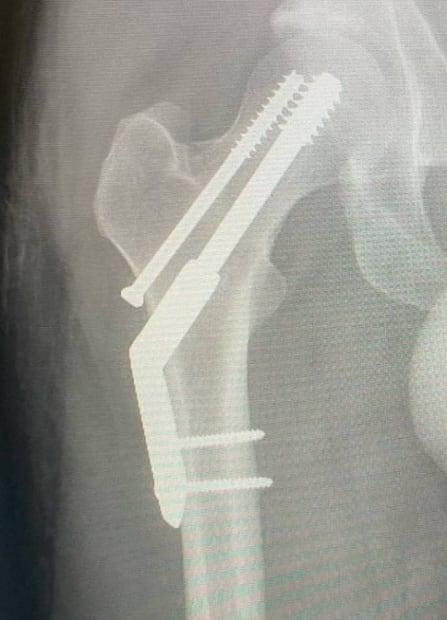

Parker sufrió de una fractura de cadera después de intentar correr un maratón, así lo relató en sus redes, donde está recibiendo el apapacho y los buenos deseos de sus fans:

"Me fracturé la cadera. Intenté correr una media maratón con lo que resultó ser una fractura por estrés. Vaya. Llegué a 1 km de la meta. Así es la vida, supongo", se lee en su mensaje que acompañó con una serie de fotografías.

Las fotos de la fractura y de cómo se está recuperando hicieron pensar a muchos que sería imposible que el grupo diera sus shows como estaba planeado, sin embargo, Kevin aseguró: "Todos los espectáculos en México y Sudamérica van adelante como lo planeé, no voy a renunciar a ustedes chicos".